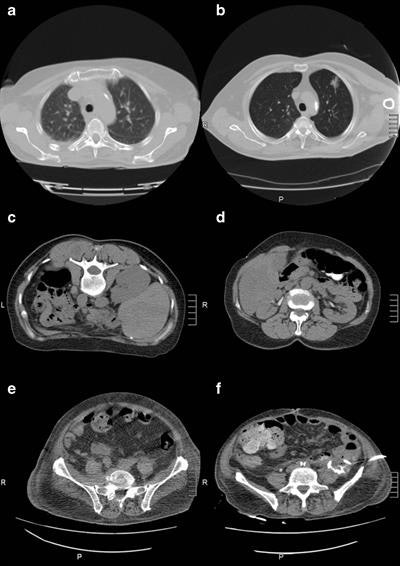

Grosser and colleagues used an iterative image reconstruction algorithm (AIDR 3D) to compare how the algorithm fared against the standard image reconstruction, filtered back projection. They included data from 165 patients (FBP = 82) with CT fluoroscopy in the thorax, abdomen, and pelvis. Noise was analyzed in a large-diameter vessel. The impact of reconstruction and variables (e.g., x-ray tube current) influencing noise and effective dose were analyzed by analysis of variance (ANOVA) and a pairwise t-test with Bonferroni-Holm correction. Three readers evaluated noise and readers' confidence.

AIDR 3D reduced the noise significantly compared with FBP (p = 0.02). The effective dose was influenced by the reconstruction, body region, interventional procedure, and x-ray tube current (all p ≤ 0.02), thus the extent of the effective dose reduction varied for different CT fluoroscopy procedures. Also, patient size (circumference) influenced image noise. For patients with a small body circumference (≤ 100 cm), AIDR 3D had a similar image noise level compared with FBP in interventions of the abdomen and pelvis. However, AIDR 3D had no significant effect in image noise levels in thorax interventions for these patients.